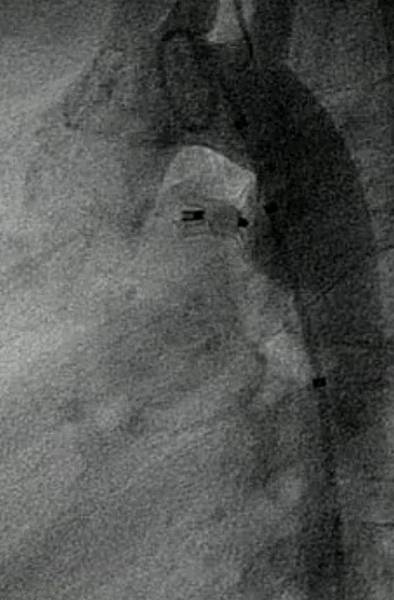

心導管關閉可以用螺旋線圈或是關閉器進行,較小的開放性動脈導管可以用螺旋線圈(一般小於2.5mm),較大的就要考慮使用關閉器。因為我們要從股靜脈或骨動脈送入關閉器或是螺旋線圈,小朋友股靜或脈股動脈的大小就是一個要考慮的因素。因此當足月嬰兒診斷開放性動脈導管,考慮他們股靜脈和股動脈血管相對較小,且前幾個月還是有自動關閉的可能性,所以如果沒有症狀或症狀不明顯,我們可能會先觀察幾個月,等長大一點再進行心導管關閉。當然,如果有症狀,我們就會考慮直接關閉。如果真的開放性動脈導管太大,手術仍然是一個可以考慮的選擇。